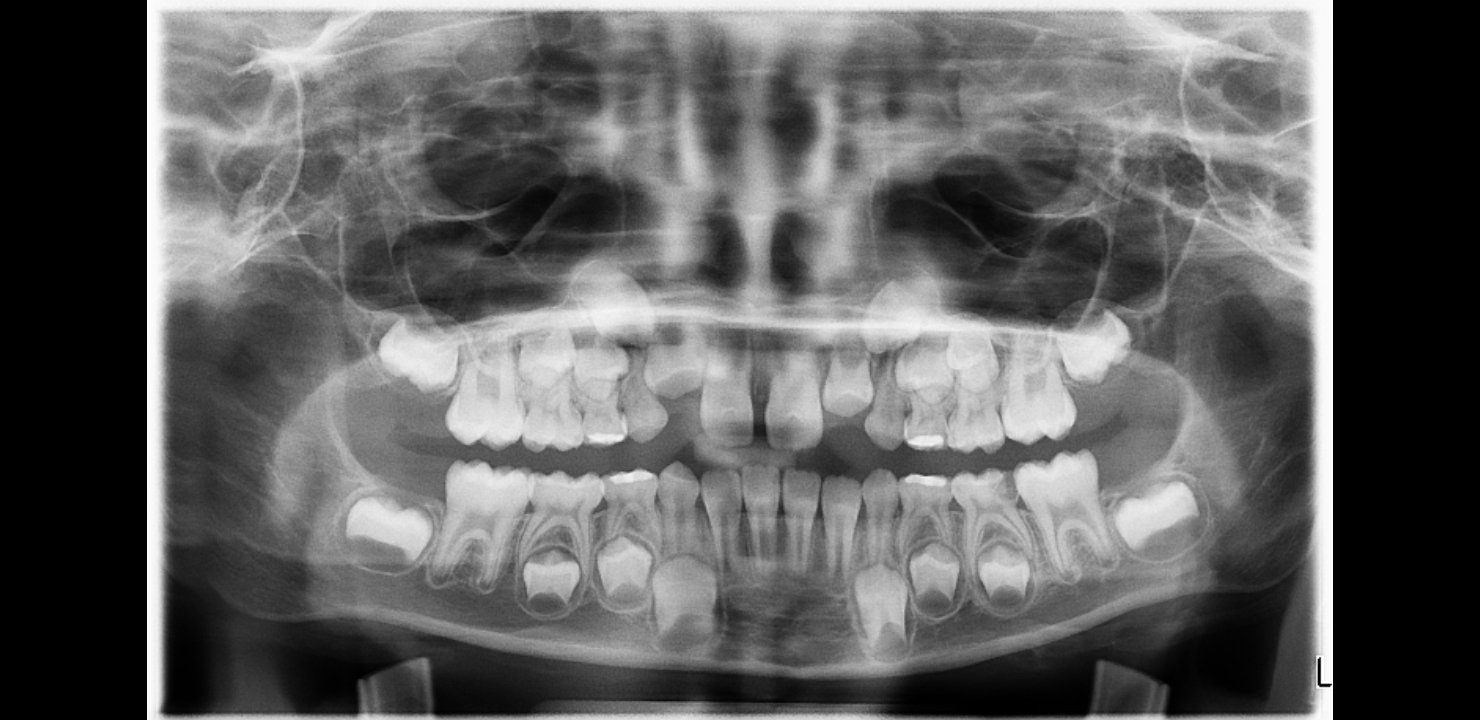

Aha, kuk, OPG syna, ake maju tie stolicky stale korene a to ma 8 rokov, nie 4...